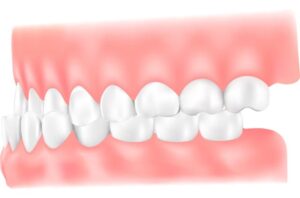

受け口(下顎前突:かがくぜんとつ)

下顎(かがく)が上顎より前に突き出ている状態のことで、噛み合わせが反対になるので「反対咬合」とも呼ばれています。上下の前歯の傾きに問題がある場合と、下顎が大き過ぎたり、上顎が小さ過ぎたりする場合とがあります。顎の大きさが原因の場合、顎の骨の成長の目途がつくまで、経過を追っていく必要があります。うまく噛めないという症状だけでなく、聞き取りにくい話し方(発音)になることも少なくありません。一般的な歯科矯正では、歯の移動によって治療を行いますが、骨格異常や噛み合わせのずれが大きい場合は、外科手術が検討されることもあります。